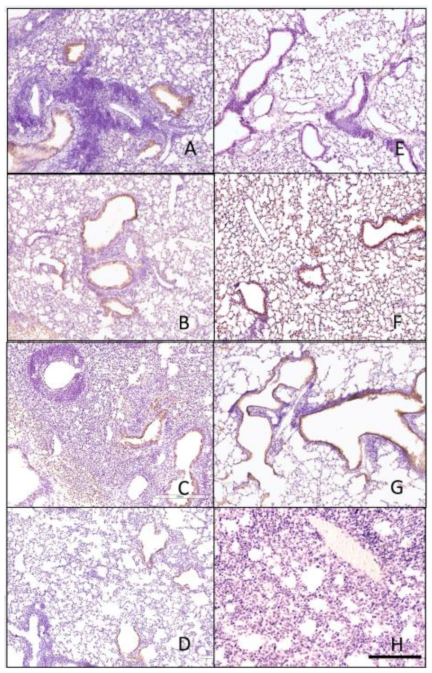

3.4. Histopathology